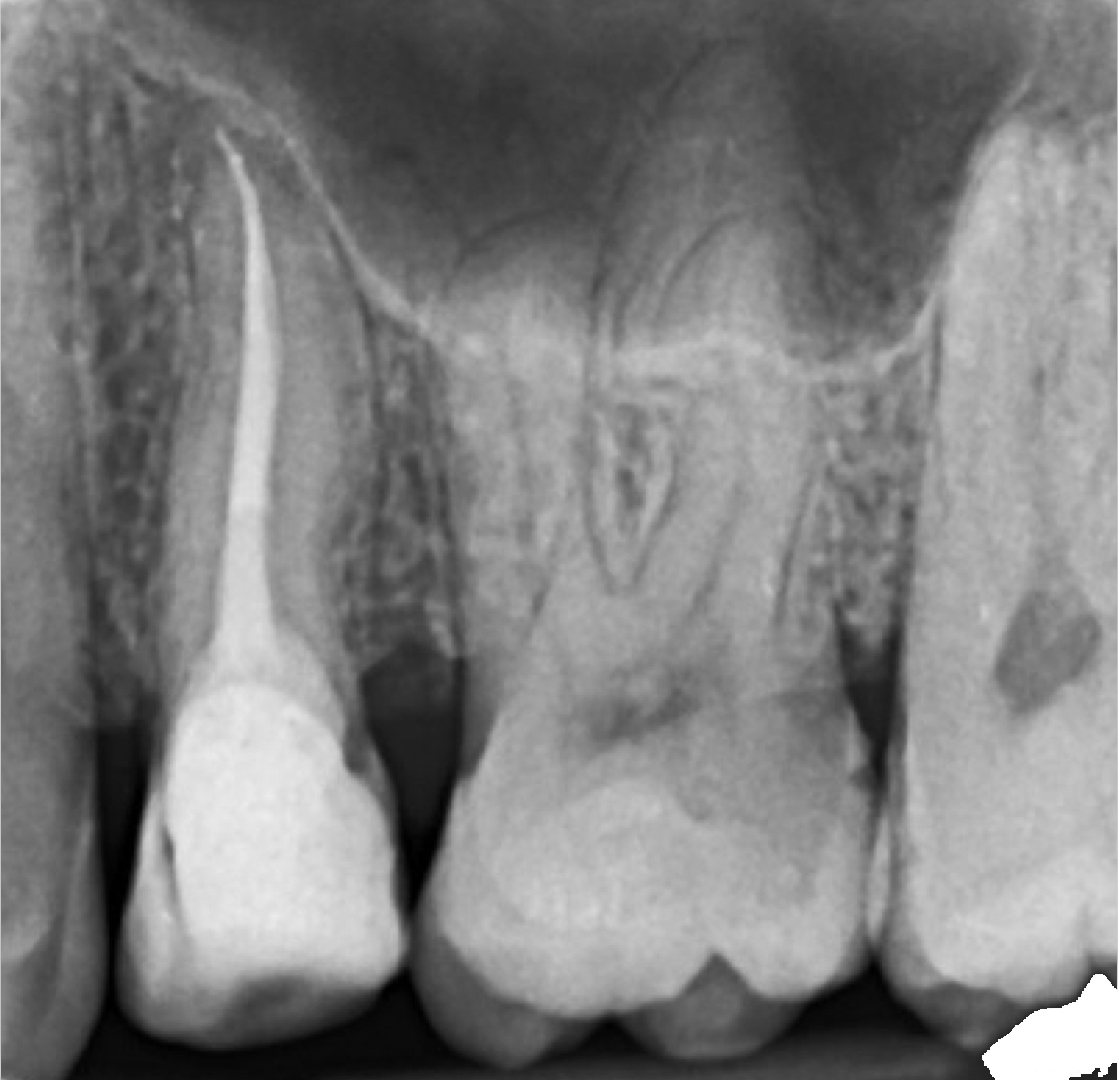

Protejarea molarului cu incrustatie onlay.